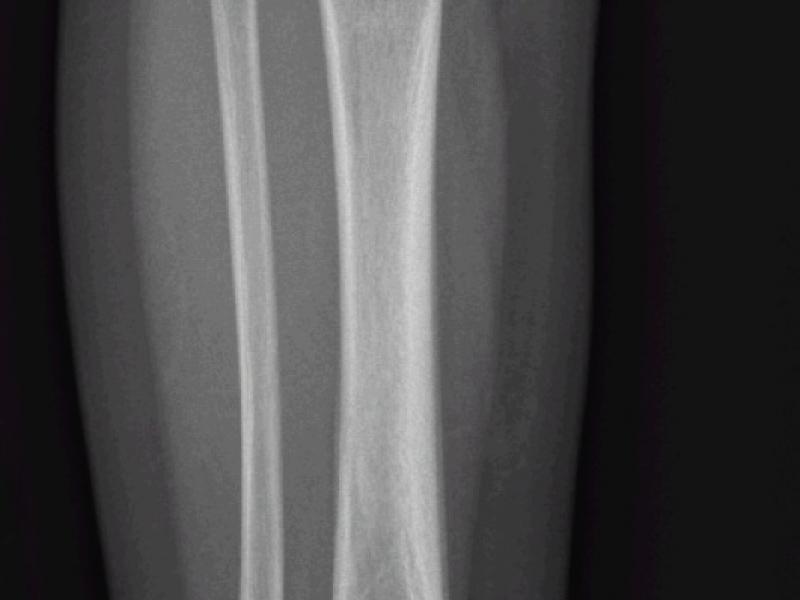

What's the diagnosis? By Dr. Michael Tom

March 03 2021

A 2 yo male presents refusing to bear weight on his right